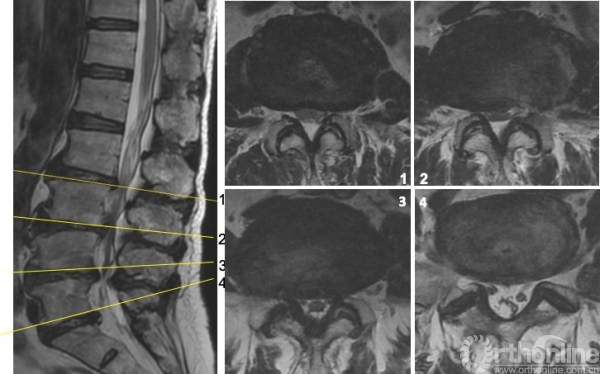

图4 术前MRI

解决方案:根据主诉、查体、辅助检查,术前需要明确致痛节段。首先,予患者局麻下行腰椎间盘造影(L2/3,L3/4,L4/5)(图5),在L3/4节段注射造影剂约2ml时,诱发出患者下腰痛症状,继续注射造影剂增加盘内压力后复制出左下肢放射痛,考虑该节段椎管空间狭小,遂予L4/5节段左椎间孔行L4出口神经根选择性神经根封闭,后患者左下肢疼痛明显缓解。

患者约2天后左下肢疼痛复现,遂于局麻下为患者实施了L3/4经皮内镜下腰椎间盘切除术,术中发现神经根与纤维环粘连,松解粘连,术后患者疼痛得到完全缓解。左侧直腿抬高试验与股神经牵拉试验转阴。术前后核磁可见该节段神经压迫解除。(图6)

图6

查体:视触动量等检查均无明显阳性体征,病理征、四肢腱反射等神经查体均正常。核磁提示:L3/4、L4/5椎管狭窄,L3/4纤维环HIZ,L4/5左侧隐窝狭窄,L5/S1纤维环HIZ。腰椎稳定性可。(图7)

图7

图8